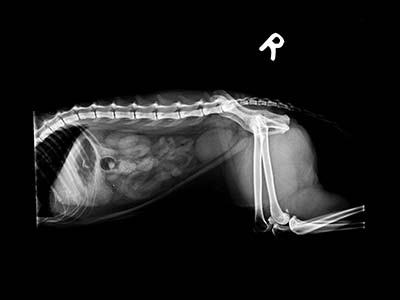

本病歷的小貓咪就是趁媽媽不在偷跑去玩線,媽媽回來後發現小貓一直乾嘔而帶來醫院就診,在X光下赫然發現胃裡有一根針!和醫師討論後手術利弊後,決定使用可以馬上回家且無創的內視鏡手術將異物取出。麻醉甦醒後,小貓很快恢復了精神活力,好像什麼都沒發生過,開開心心的回家了。

X光可以看到胃中有一根針

仰照也可以看到針的位置